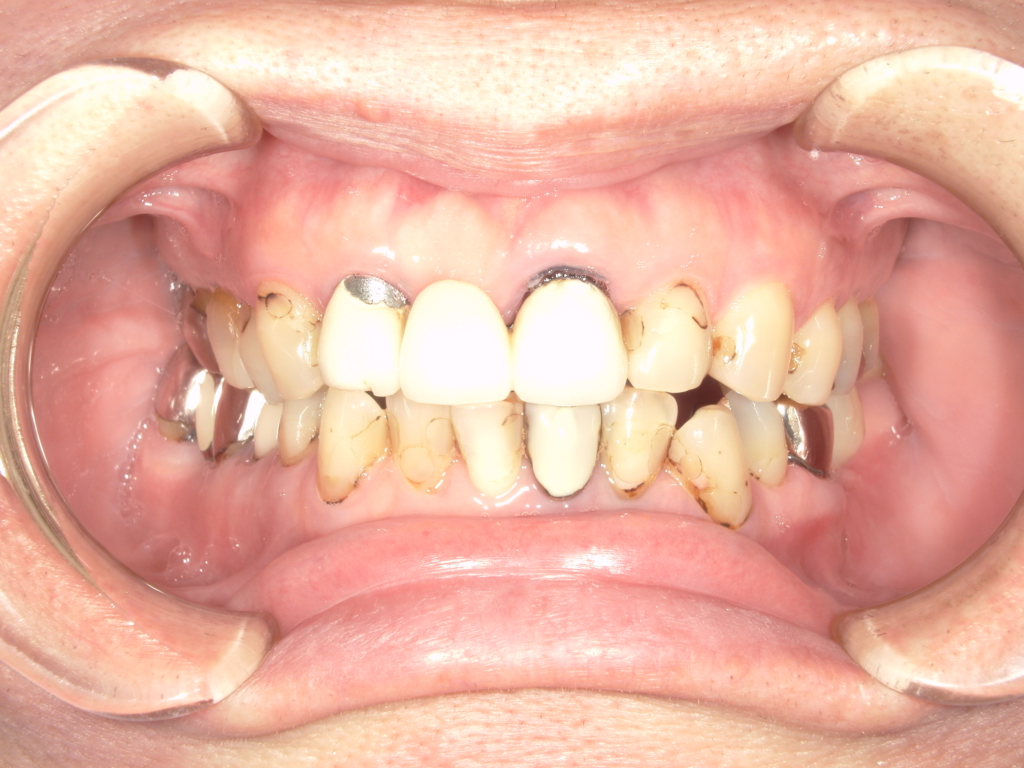

Y様インプラント実例 #44

左の上下の奥歯をインプラントで治療しています。

左下の奥歯は歯を抜くのと同時にインプラントの埋め込みを行っています。

被せものは上下、セラミックスで作っています。

治療前

治療後